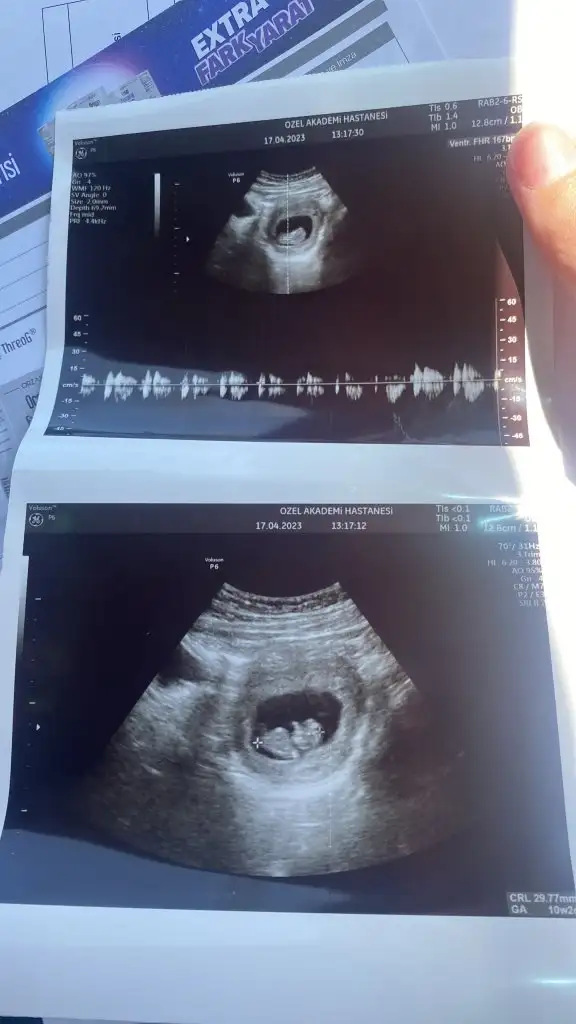

Karından görüntüyse erkek vajinal görüntüyse kız :)6+3 canım benimkinde bakabilir misin rica etsem

Bana da yorum yapabilir misiniz 9.hafta karındanKarından görüntüyse erkek vajinal görüntüyse kız :)

Karındansa kız vajinal görüntüyse erkek :)Bana da yorum yapabilir misiniz 9.hafta karından

Şöyle burda bebek ve plesantası çok ortada çıkmış maalesef anlayamadım. Sağda olunca kız solda olunca erkek oluyor karından ultrasondaBu da 10 haftalık hali hala kız mı diyorsunuz peki ?ManyakPrenses

Merhaba karından ultrasonda erkek vajinalse kız canım